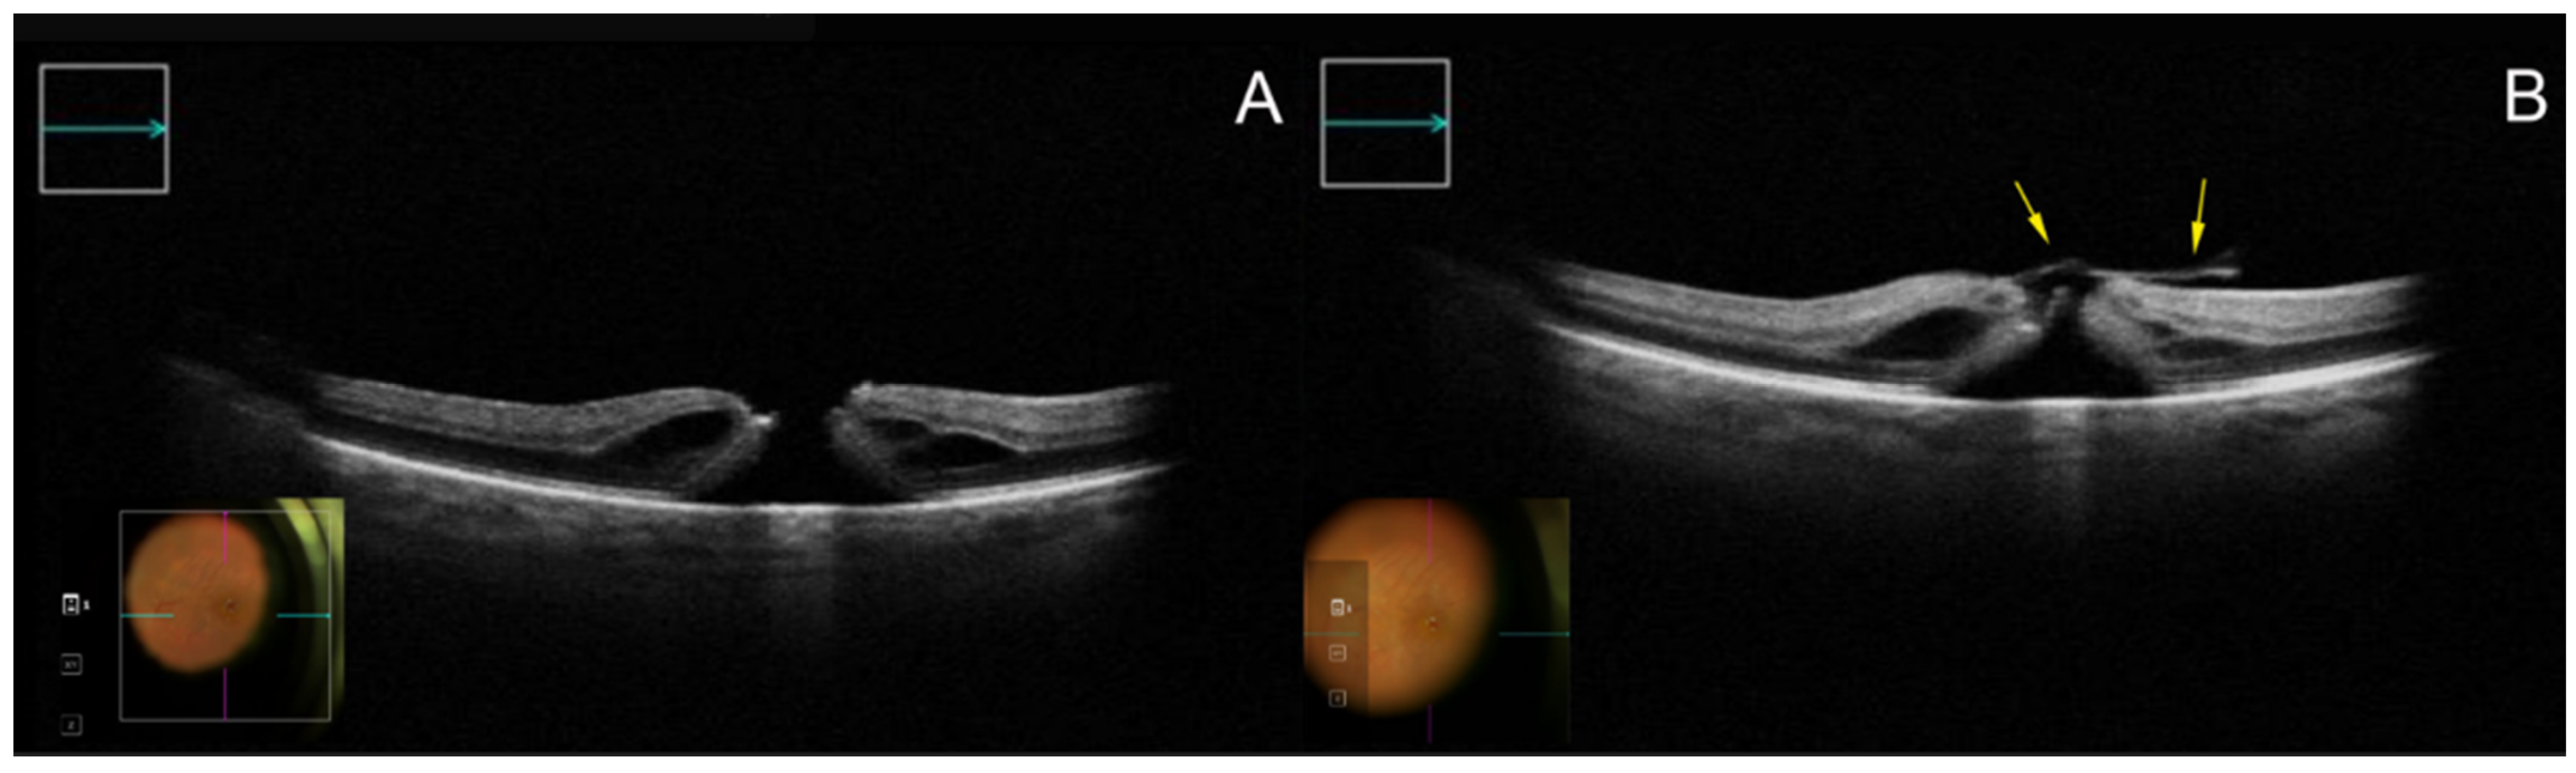

Figure 1. Appearance of an FTMH on iOCT before (A) and after (B) preparation of the temporal inverted ILM flap (yellow arrows) viewed through a horizontal cross-section (green arrow). Abbreviations: FTMH, full-thickness macular hole; iOCT, intraoperative optical coherence tomography; ILM, internal limiting membrane.